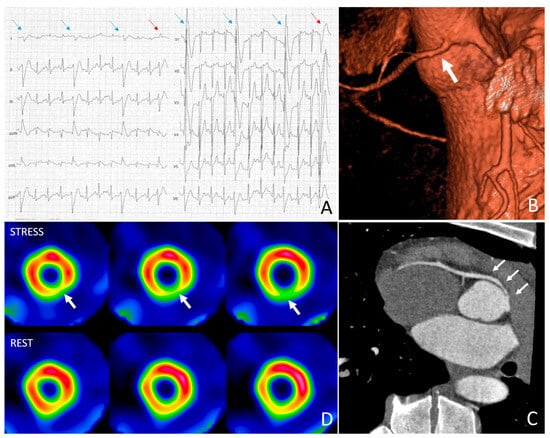

4.1. Athlete with Positive Exercise Testing and Moderate Coronary Stenosis

4.2. Athlete with Positive Exercise Testing and Myocardial Bridging